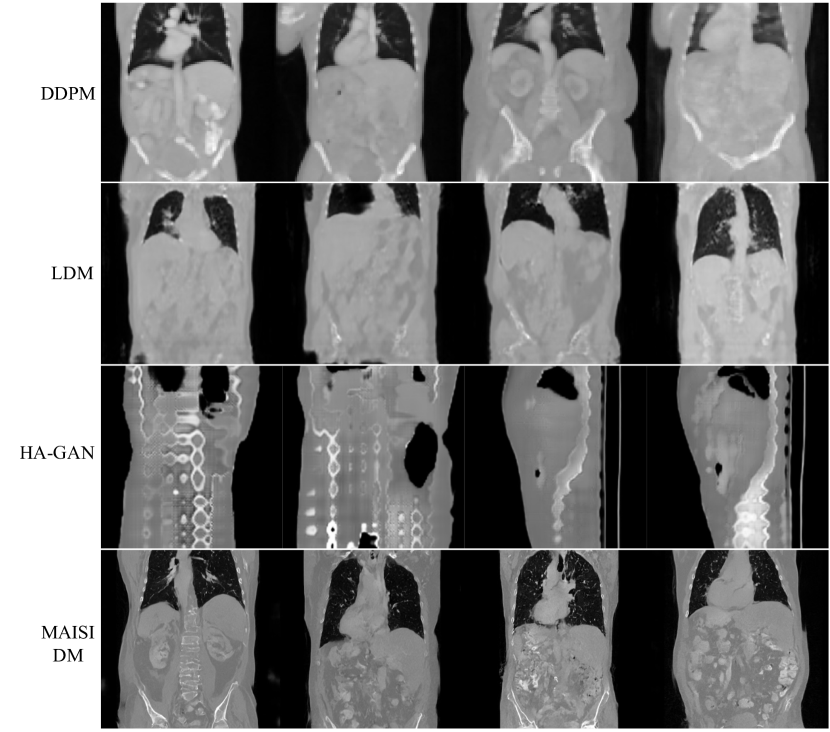

4.3 Evaluation of MAISI Diffusion Model

- Synthesis quality : 실제 dataset과 비교하였을 때 FID 수치 비교

- DDPM, LDM, HA-GAN과 비교하였을 때 실제 dataset과 유사한 이미지를 생성.